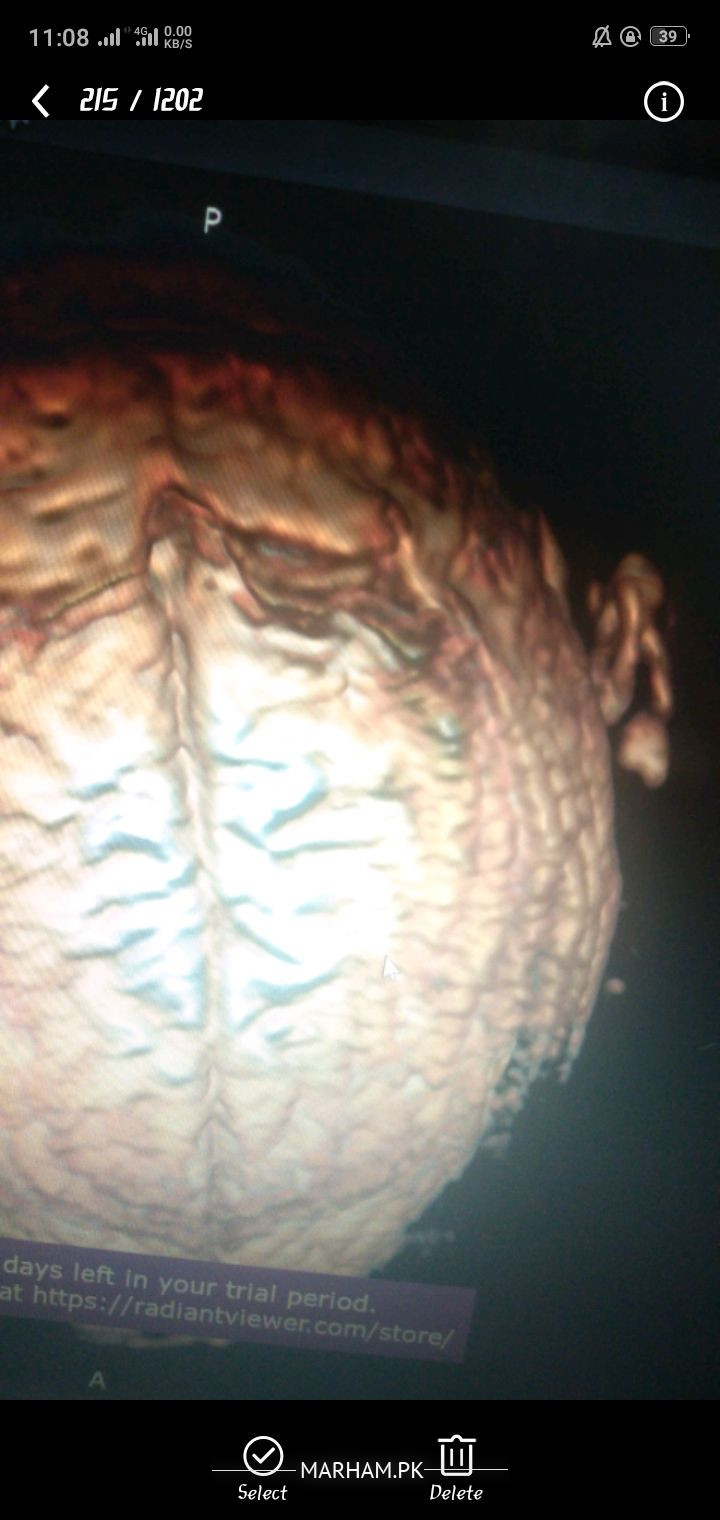

Im 23 years male diagnosed with CVST. I was having pain (10/10) on the left side of back head. Visited differnt hospital most of them give medcines by saying that it's due to hot weather or due to night job. All of a sudden one night i was suffered from unbearable pain and went to agha khan hospital they did CT scan, MRI and diagnosed it. was Admitted in april is it treatable? do i have any other major or minor brain problem besides cvst? how much time it'll gonna take? should i take it seriously? what threats do i have and what to care about? anything to worry about? I've bunch of other reports as well along with and have DVD of MRI and CT scan let me know if you need the film. Drs. are saying it's due to smocking, dehydration, blood is way too much densed I've that report as well where the blood components are written along with there values. am i taking the rights meds (asking just for self satisfaction)

pic 1